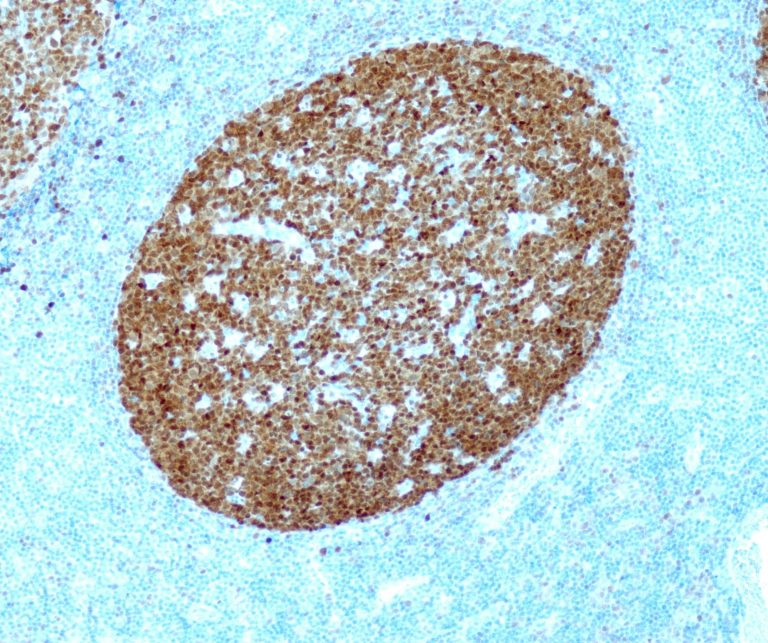

Vascular Pathology

Gastrointestinal (GI) Pathology

General Marker

Breast Pathology

Endocrine Pathology

Gynecological Pathology

Neuropathology

Infection Markers

Lung Pathology

Urinary Tract Pathology

Transplantation Pathology

Soft Tissue Pathology

Hematopathology